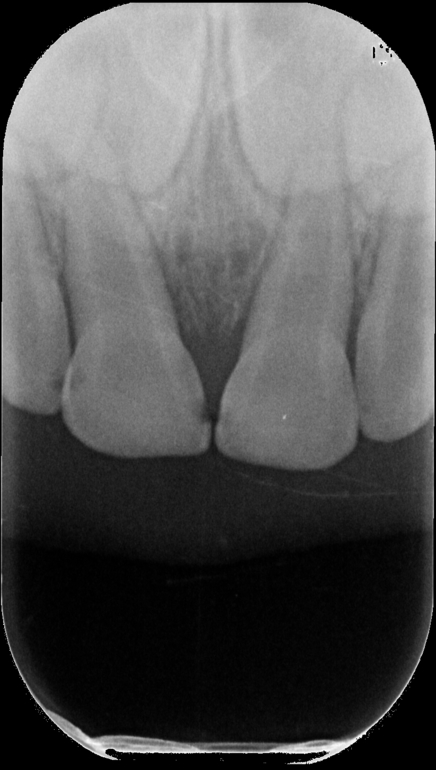

3 недели назад дочь упала передними зубками, отекла губа, шла кровь. Были на море и к специалисту не обратились. Зубки стали болеть, через неделю-1,5 заметили, что зубки потемнели (не черные, но серые).

Были у одного стоматолога, сделали снимок, сказали, что воспаление небольшое вокруг зубиков, корень не травмирован, надо следить и ждать.

Другой стоматолог сделал снимок и сказал, что надо срочно вскрывать и чистить (что наличие кариеса усугубляет обстановку), но не факт, что и после чистки удасться спасти зубки. Чем скорее, тем лучше.